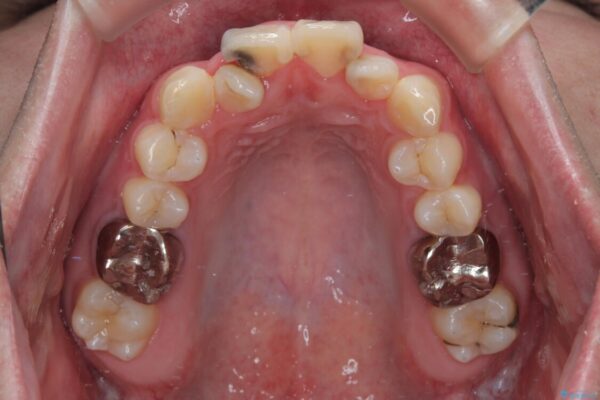

初診時の状態

・上下ともに歯がきれいに並びきらず、がたつきが見られました。

・上下の前歯の中心(正中)がずれています。

・特に上顎の幅が狭いため、下顎の歯列も内側に入り込み、歯が並ぶスペースが不足していました。

治療方針

このような歯列の狭さに起因するデコボコを改善するために、**MARPE(骨に固定する上顎急速拡大装置)**を使用して、上顎の横幅を拡大し、これにより歯が並ぶためのスペースを確保し、メタルブラケットを用いて歯列を整えていく計画としました。

治療前

• 1年でここまで変わる!歯列のがたつきと正中のズレを改善した矯正治療(メタルブラケット×MARPE) 治療前画像